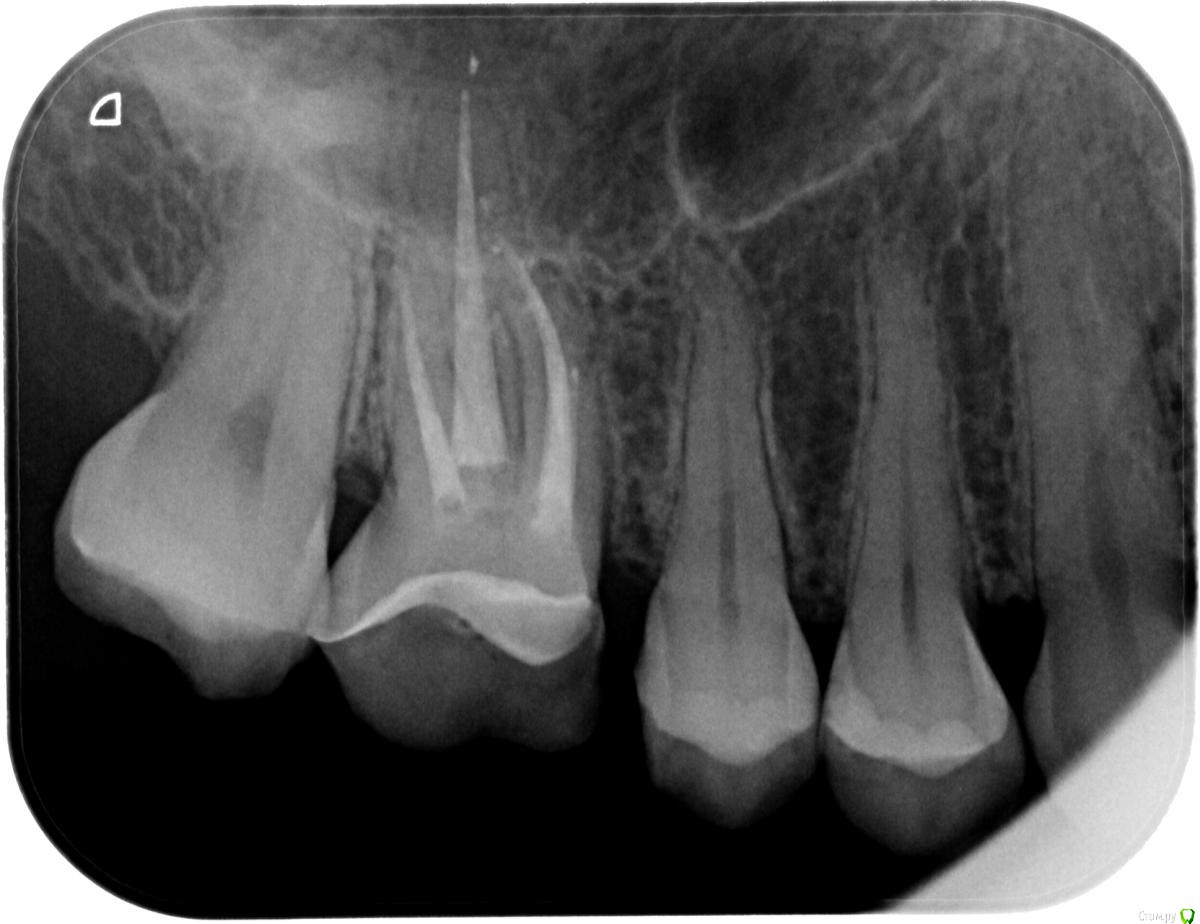

pocaba Опубликовано 9 июля, 2018 Автор Поделиться Опубликовано 9 июля, 2018 (изменено) Я тогда, наверное, для информативности приложу снимок до установки штифта (январь 2018).Если действительно при распломбировке канала произошла перфорация корня и штифт вышел за пределы зуба, то что мне, по вашему мнению, имеет смысл предпринять как пациенту? Взять направление на КТ? Целесообразно ли будет попросить врача не делать циркониевую коронку, а установить на постоянный цемент временную пластмассовую, которую я сейчас и ношу на временном цементе?Вообще, во время установки штифта местной анестезии не было, и я не почувствовала хруста или каких-либо ощущений под зубом, как, например, было при перелечивании у эндодонта каналов этого же зуба гуттаперчей пару лет назад (тогда аж до слёз). Неужели возможно нисколько не почувствовать настолько вышедший за пределы зуба штифт при его установке? Изменено 9 июля, 2018 пользователем pocaba Ссылка на комментарий

St. Опубликовано 10 июля, 2018 Поделиться Опубликовано 10 июля, 2018 На снимке до все выглядит прилично. Взять направление на КТ? да, это как минимум разрешит все Ваши сомнения.И в зависимости от его результатов или оставлять временную и понаблюдать как будет зуб вести себя дальше или ставить постоянную Неужели возможно нисколько не почувствовать настолько вышедший за пределы зуба штифт при его установке? Нет, вы неправильно поняли мой ответ. Доктор спрашивал о направлении штифта. И на картинке я нарисовала как мне видится положение штифта и пломбировочного материала. Все это в пределах корня зуба. Ссылка на комментарий

pocaba Опубликовано 11 июля, 2018 Автор Поделиться Опубликовано 11 июля, 2018 (изменено) На снимке до все выглядит прилично. да, это как минимум разрешит все Ваши сомнения.И в зависимости от его результатов или оставлять временную и понаблюдать как будет зуб вести себя дальше или ставить постоянную Нет, вы неправильно поняли мой ответ. Доктор спрашивал о направлении штифта. И на картинке я нарисовала как мне видится положение штифта и пломбировочного материала. Все это в пределах корня зуба. Большое спасибо St., теперь стало гораздо понятнее.Стоматолог непосредственно перед постановкой штифта рентгеновские снимки, к сожалению, не видел: оказалось, что ассистентка забыла их сохранить с моей флешки после первого приёма, а я в этот момент уже сидела на кресле с раскрытым коффердамом. Доктор сказал, что "ну да ничего страшного, так поставим". После установки штифта контрольный снимок он тоже не делал. Пока что удалось сделать только ОПТГ, а приём у врача я перенесла на эту пятницу. Пульсация под зубом в последние дни больше не беспокоила.Скажите, пожалуйста, если штифт действительно стоит не совсем в проекции канала, то означает ли это, что он был установлен некорректно и такая конструкция малонадёжна? Повышает ли это вероятность того, что треснет корень или разовьётся инфекция? Я в полной растерянности и не знаю, стоит ли мне дальше продолжать работу над этим зубом: у частных итальянских стоматологов нет такого понятия, как "гарантия", и бесплатное либо недорогое устранение каких-то неожиданностей вроде вылетевшей коронки со штифтом зависит только от доброй воли и совести врача. ОПТГ зуб 16 крупным планомОПТГ целиком Изменено 11 июля, 2018 пользователем pocaba Ссылка на комментарий

St. Опубликовано 11 июля, 2018 Поделиться Опубликовано 11 июля, 2018 Пульсация под зубом в последние дни больше не беспокоила. Это уже хорошо! если штифт действительно стоит не совсем в проекции канала, то означает ли это, что он был установлен некорректно и такая конструкция малонадёжна? На этот вопрос сложно однозначно ответить, т.к. все очень индивидуально. Я в полной растерянности и не знаю, стоит ли мне дальше продолжать работу над этим зубом Не паникуйте, чего-то совсем катастрофического скорее всего нет.Если все успокоилось походите какое-то время с временной коронкой и если все ок протезируйте постоянно. Пока что удалось сделать только ОПТГ Для выяснения этих вопросов панорамный снимок не информативен Ссылка на комментарий